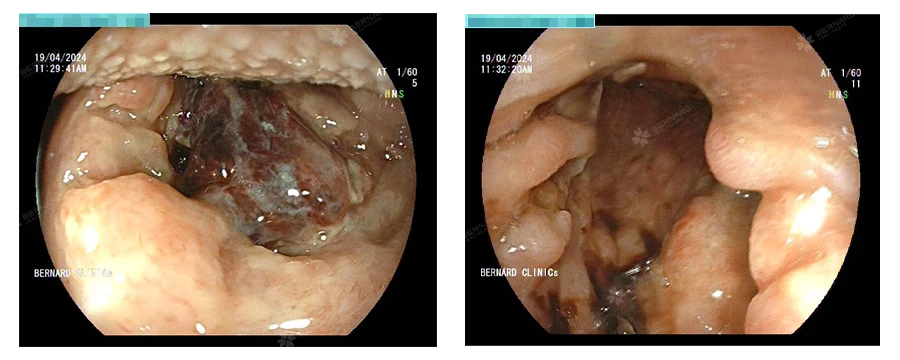

Sau khi được tiếp nhận và thăm khám sơ bộ, bà S. được tư vấn thực hiện nội soi khảo sát khu vực thực quản - vùng hầu họng - vòm họng để đánh giá trực quan hơn.

Kết quả ghi nhận: Tại vùng họng bên trái có tổn thương chồi sùi loét, đang chảy máu và có tụ mảng máu bầm xung quanh, theo dõi ung thư vòm họng đang xuất huyết.